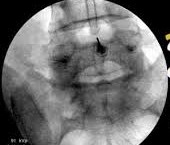

Η διατρηματική επισκληρίδιος έγχυση αποτελεί μια πιο εξειδικευμένη ιατρική πράξη, η οποία εφαρμόζεται κάτω από ακτινοσκοπικό έλεγχο και με χρήση σκιαγραφικής ουσίας για την απεικόνιση του νεύρου, όπου μικρή ποσότητα τοπικού αναισθητικού και κορτιζόνης εγχέεται απευθείας στο νευρικό τρήμα που αποτελεί το σημείο εξόδου του νεύρου από την σπονδυλική στήλη.